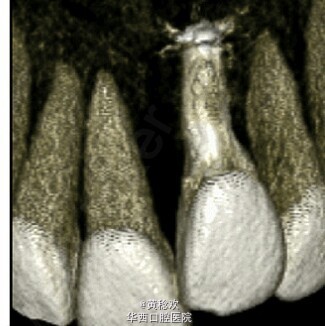

牙齿脱位对牙周膜、牙槽骨、牙龈、牙髓和牙骨质造成严重损害。脱位牙再植后经常伴有牙骨粘连等并发症。牙骨粘连指的是局部牙骨质和周围牙槽骨融合,多起因为牙齿正在萌出过程中或萌出后受到机械性、温度或者代谢产物刺激,对牙周膜造成损伤,好发于恒切牙。 牙骨粘连可通过临床和放射片检查诊断。临床检查包括低咬合状态、叩诊和松动度测试,最明显的特征是即便该牙施加正畸牵引力后也无法移动。整个牙的牙骨粘连可以通过放射片显示,其特征为无明显的牙周膜影响。但是如果该牙只有颊侧或者舌侧粘连,放射片上很难判断。近年来,CBCT的引入,可以逐渐将放射检查视野拓宽到3D层面,增强了对骨牙粘连的准确性。治疗骨牙粘连的方案包括:拔除、截冠、修复、手术半脱位、骨切开术和牵张成骨术等。